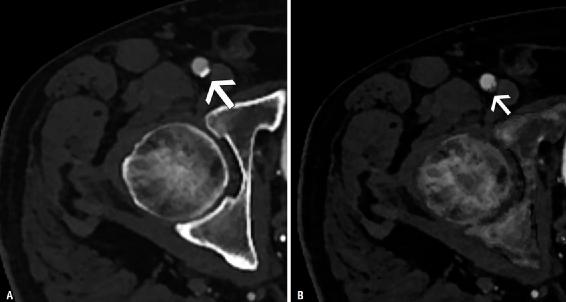

开花(Blooming )伪影是由具有不同组织的体素中衰减值的部分容积平均引起的图像伪影,使得难以分辨小于体素的对象。由于CT系统的空间分辨率有限,钙化晕状伪影是心血管检查中常见的伪影。开花伪影是心血管成像中的一个重要挑战,尤其是在具有钙或支架的小血管(例如冠状动脉、远端动脉)中,因为放射科医生试图将这些结构与造影剂填充的管腔区分开。因此,钙化斑块(以及金属支架)似乎大于其真实尺寸,导致对管腔狭窄的高估,这可能导致不适当的临床管理。PCD可以通过多种方式解决钙化的开花问题。随着空间分辨率的提高,可以通过减少体素大小和部分容积来改善钙化的晕状伪影,从而提高密集血管钙化患者狭窄评估的准确性(图12)。或者,也可以通过增加X射线能量降低体素的平均衰减来减少钙化晕状伪影,这可以在PCD-CT中利用高能VMI实现。最后,可以使用材料分解算法从图像中分离钙化,该算法可以使用多能量信息创建,潜在地提供管腔狭窄的更精确估计(图13)。

图12 74岁男性患者,患有已知的外周动脉疾病。A、B 外周动脉疾病患者的轴位重建在能量积分探测器CT上显示胫前动脉中有钙晕(箭头A)。与能量积分探测器CT重建(A)相比,同一患者在同一水平上的光子计数探测器CT重建显示出胫骨前动脉(箭头,B)中钙斑的可视化显著改善,因此可以更好地评估管腔直径。